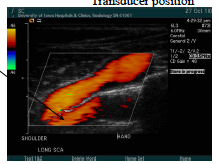

where is the Td placed to get the subclavian?

lateral window